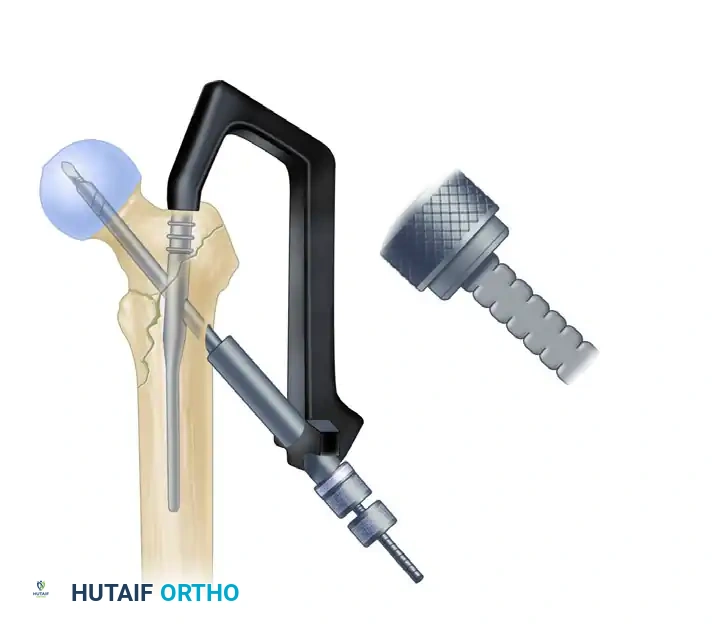

5. Lag Screw Placement and Compression

Achieving optimal lag screw placement is the most critical factor in preventing mechanical failure (cut-out). The goal is a Tip-Apex Distance (TAD) of less than 25 mm.

- Insert the lag screw over the guide pin until the threads are fully engaged in the subchondral bone of the femoral head.

- Use the centering sleeve insertion device to advance the centering sleeve over the lag screw shaft, locking it into the nail.

- Applying Compression: Before applying compression, release the traction on the fracture table. This allows the fracture fragments to settle. Insert the compression screw through the top of the nail and apply the desired amount of linear compression across the fracture site.